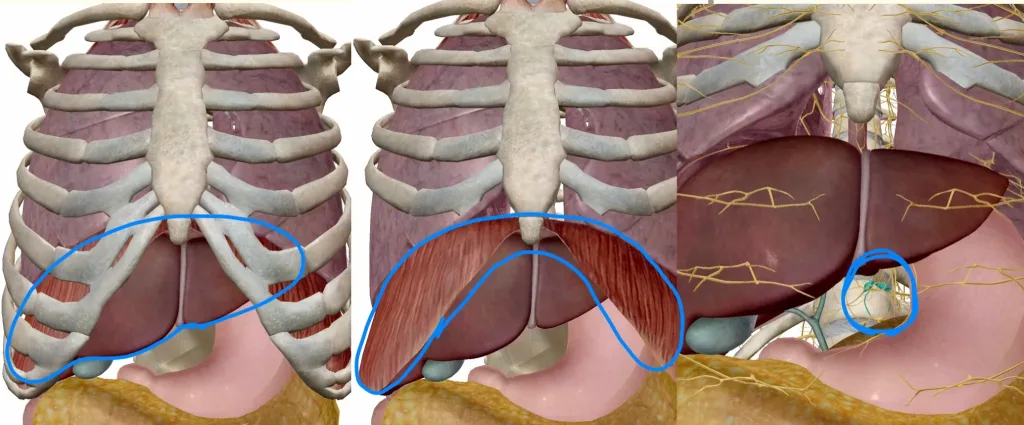

肝臓は左の図が示すように、肋骨に守られるように存在している臓器です。身体の右側を占める割合が多いのが特徴です。肝臓の真上には横隔膜、さらにその上には肺があり、息を吸った際には肺が膨らむことで肝臓の右側は肋骨から下へ少しはみ出るようになります。

横隔膜は真ん中の図が示すように、肝臓に覆い被さる形のドーム状をしている筋肉です(焼肉で言うところのハラミとサガリに相当します)。この図では見やすいように一部肋骨を消して表示しております(=横隔膜もまた、肋骨の内側に存在しております)。横隔膜が収縮することで、肺が下に引き延ばされて空気を取り入れることができます。呼吸は横隔膜の収縮、弛緩を繰り返すことで行われます。

腹腔神経叢は右の図が示すように、身体の奥深くに存在します。神経叢(しんけいそう)とは神経の細胞が集まる交差点のようなものです。この図は肝臓のある位置を少し下から覗いたような角度で腹腔神経叢を除いています。本来であれば周囲には大血管や膵臓がありますが、わかりやすいように消して表示しています。このように腹腔神経叢は身体の奥深くに存在しています。